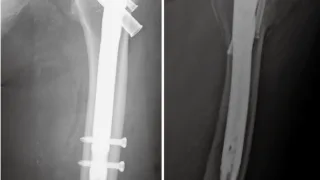

大腿骨頚部骨折の闘病日記

手術日+727日目 2026/2/24(火)(骨折から2年)